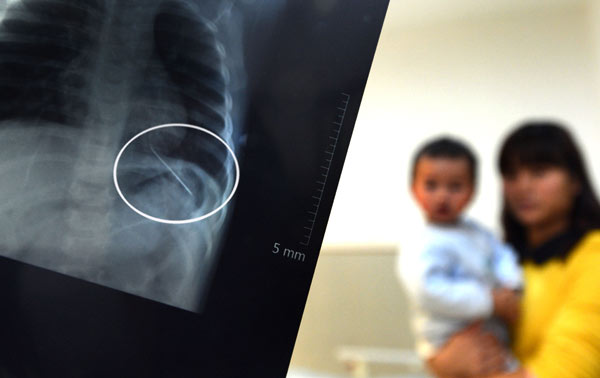

An X-ray shows a needle that was found inserted into the left lung of a 14-month-old boy in Nanjing, Jiangsu province, on Monday. Shi Xianghui / For China Daily |

Doctors took an X-ray of his chest and were shocked to find a needle-shaped metal object in his lung.

"It was dangerous because the pinpoint was positioned outside the lung and could have moved toward the heart," Mo said.